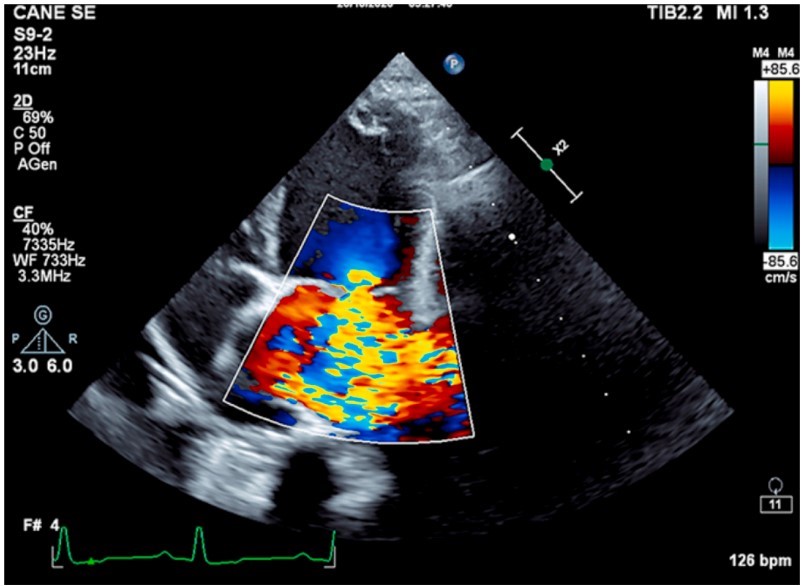

به خوبی شناخته شده است که اکوکاردیوگرافی استاندارد طلایی برای بررسی قابل اعتماد ساختار و عملکرد قلب و عروق در انسان است. با پیشرفت اکوکاردیوگرافی بالینی، روش ها و تجهیزات از انسان به حیوانات کوچک گسترش یافته است. تصویربرداری اولتراسوند به ارزیابی عملکرد قلب کمک می کند. حیوانات کوچک، و اجازه ارزیابی آناتومی و عملکرد قلب بدون ایجاد استرس قابل توجه به بیمار را می دهد. در سگها و گربهها، اکوکاردیوگرافی به شناسایی نقایص آناتومیک مادرزادی مانند مجرای شریانی پایدار (PDA)، تنگی دریچه ریوی/آئورت، نقص دیواره بین دهلیزی/بطنی، سهگانه/تترالوژی فالوت کمک میکند. علاوه بر این، اطلاعاتی در مورد گرادیان فشار در عروق بزرگ برای ارزیابی مناسب گردش خون قلب-ریه می دهد. مطالعات طولی برای ارزیابی گرادیانهای فشار عروقی و استراتژیهای درمان پزشکی ممکن و ضروری است. یکی از شایع ترین بیماری هایی که دریچه های قلب را در سگ ها تحت تاثیر قرار می دهد، اندوکاردیوز دریچه میترال است (شکل 5). بیماری دژنراتیو دریچه میترال (DMVD) یک سگ شایع است.

شکل5. اندوکاردیوز دریچه میترال در یک زن 10 ساله کاوالیر کینگ چارلز اسپانیل. داپلر رنگی در اسکن آپیکال چهار حفره ای نارسایی دریچه میترال را مشخص می کند.

تقریباً 30 درصد از سگ های بالای 10 سال به این بیماری مبتلا می شوند که منجر به نارسایی میترال می شود. اکوکاردیوگرافی استاندارد طلایی برای ارزیابی ساختار و عملکرد قلب است و همراه با الکتروکاردیوگرافی و رادیوگرافی قفسه سینه به ابزار مهمی در ارزیابی می شود. پیشرفت بیماری را نشان می دهد و نشانه هایی را برای ارزیابی مناسب استراتژی های درمان پزشکی ارائه می دهد. سونوگرافی اسکلتی عضلانی یک زمینه به سرعت در حال رشد در دامپزشکی است. سونوگرافی برای اختلالات اسکلتی عضلانی معمولاً در پزشکی ورزشی اسب و طب انسانی استفاده می شود و امروزه به دلیل افزایش تشخیص آسیب های بافت نرم در بیماران حیوانات کوچک نیز بیشتر انجام می شود. مزایای سونوگرافی اسکلتی عضلانی در امکان کاوش است. همچنین اندام طرف مقابل، برای ارزیابی تقارن ساختارهای تاندون، و تکرار سونوگرافی برای ارزیابی روند بهبود. افزایش مسابقات ورزشی که خواستار قدرت بدنی هر چه بیشتر سگ ها است، منجر به افزایش آسیب های اسکلتی عضلانی شده است. بیماری های شانه شامل تاندون عضله دو سیپیتال به عنوان تاندونیت/پارگی جزئی (شکل 6)،عضله بالای خاری و عضله زیر خاری تحت تاثیر پارگی نسبی، و برداشتن استخوان انتهایی تاندون از شایع ترین آسیب های مشاهده شده است. میوزیت مزمن عضلات ایلئوپسوآس باید به عنوان یک بیماری معمولی در نتیجه مسابقات ورزشی سگ ذکر شود. در میان این بیماری ها سایر شرایط پاتولوژیک که می توان از نظر سونوگرافی در نظر گرفت شامل پارگی عضلات، نئوفرماسیون عضلانی (گرانولوم/آبسه/نئوپلازی)، استئوآرتریت و بیماری های تاندون/رباط (التهاب، پارگی جزئی/کامل) می باشد.